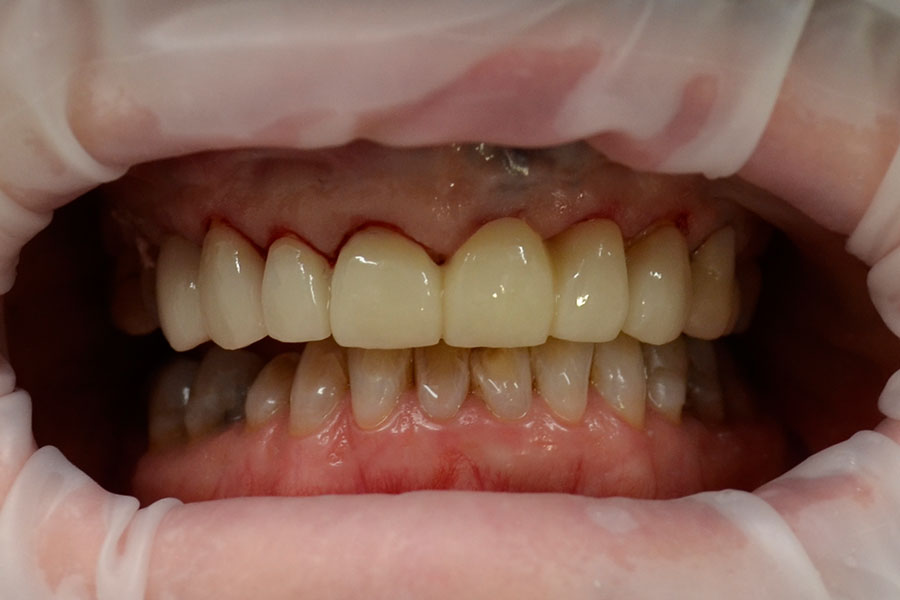

Christine had a crown on a root canal treated upper right central incisor that had a receding gum line.

Some of the white fillings on other front teeth were also stained. Pauline decided to have the crown replaced and ceramic veneers placed on other three adjacent teeth. The new crown is all ceramic and blends in more naturally with the veneers.